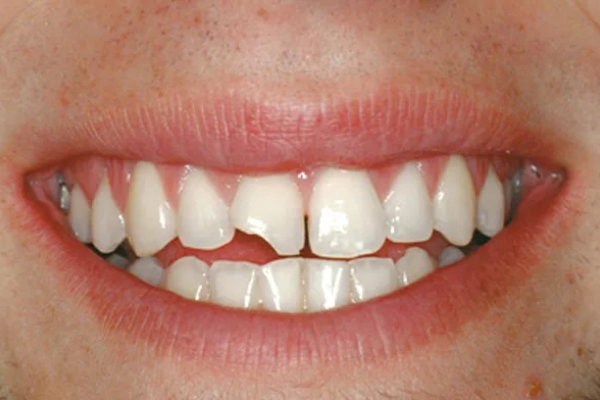

Mẻ răng cửa không chỉ gây mất thẩm mỹ cho hàm răng mà còn ảnh hưởng đến tự tin khi giao tiếp. Nó cũng làm cho việc ăn uống trở nên khó khăn và làm mất đi cảm giác ngon miệng khi ăn. Vì vậy, việc khắc phục tình trạng này cần được thực hiện sớm để tránh các vấn đề tiềm ẩn.

Răng cửa là điểm nhấn quan trọng của một nụ cười lôi cuốn. Khi răng cửa bị mẻ, không chỉ là vẻ đẹp tự nhiên bị suy giảm mà còn khiến cho hàm răng mất đi sự đồng đều và đều màu. Cảm giác tự ti và sự ngại ngùng khi giao tiếp có thể nảy sinh từ việc này, khiến cho bạn có thể cảm thấy không tự tin trong các tình huống xã hội. Sự tự tin và sự thoải mái với bản thân, trong khi đó, lại là yếu tố quan trọng ảnh hưởng đến chất lượng cuộc sống của mỗi người.